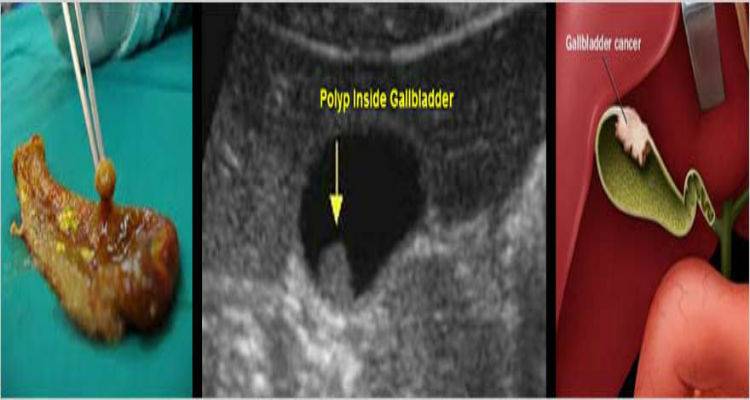

Οι πολύποδες στη χοληδόχο κύστη, αποτελούν πλέον πολύ συχνό φαινόμενο, που αποκαλύπτεται «τυχαία» στην ολοένα και πιο συχνή υπερηχογραφική μελέτη του ήπατος, ως μέσο προληπτικού ελέγχου. Παρουσιάζεται σε ποσοστά 4,3-7% στις ηλικίες άνω των 45 ετών, με μεγαλύτερη πιθανότητα στους άνδρες.

- Οι αδενωματώδεις πολύποδες ή αδενώματα, οι οποίοι αποτελούν την μόνη πιθανή αιτία εξαλλαγής σε αδενοκαρκίνωμα της χοληδόχου κύστεως, το οποίο αποτελεί και τον κακοηθέστερο και πλέον επιθετικό καρκίνο του γαστρεντερικού συστήματος. Αναπτύσσονται από 5 έως 20 χιλιοστά και κατά κανόνα είναι μονήρεις.

- Η διάγνωση των πολυπόδων είναι κατά κανόνα υπερηχογραφική. Αποτελεί την πλέον ενδεικνυόμενη, φθηνή και λεπτομερή μέθοδο διάγνωσης αλλά και παρακολούθησής τους.